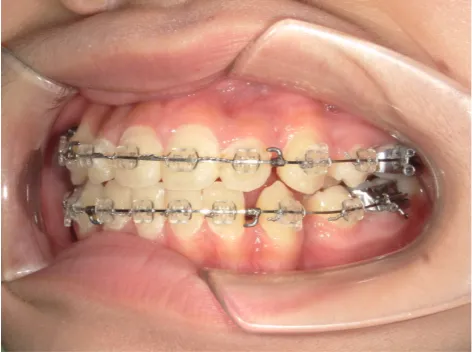

治療中⑧高1:15y11m 抜歯治療中

治療中⑨高2:17y1m 抜歯治療中

治療後⑩高2:17y7m 抜歯治療終了